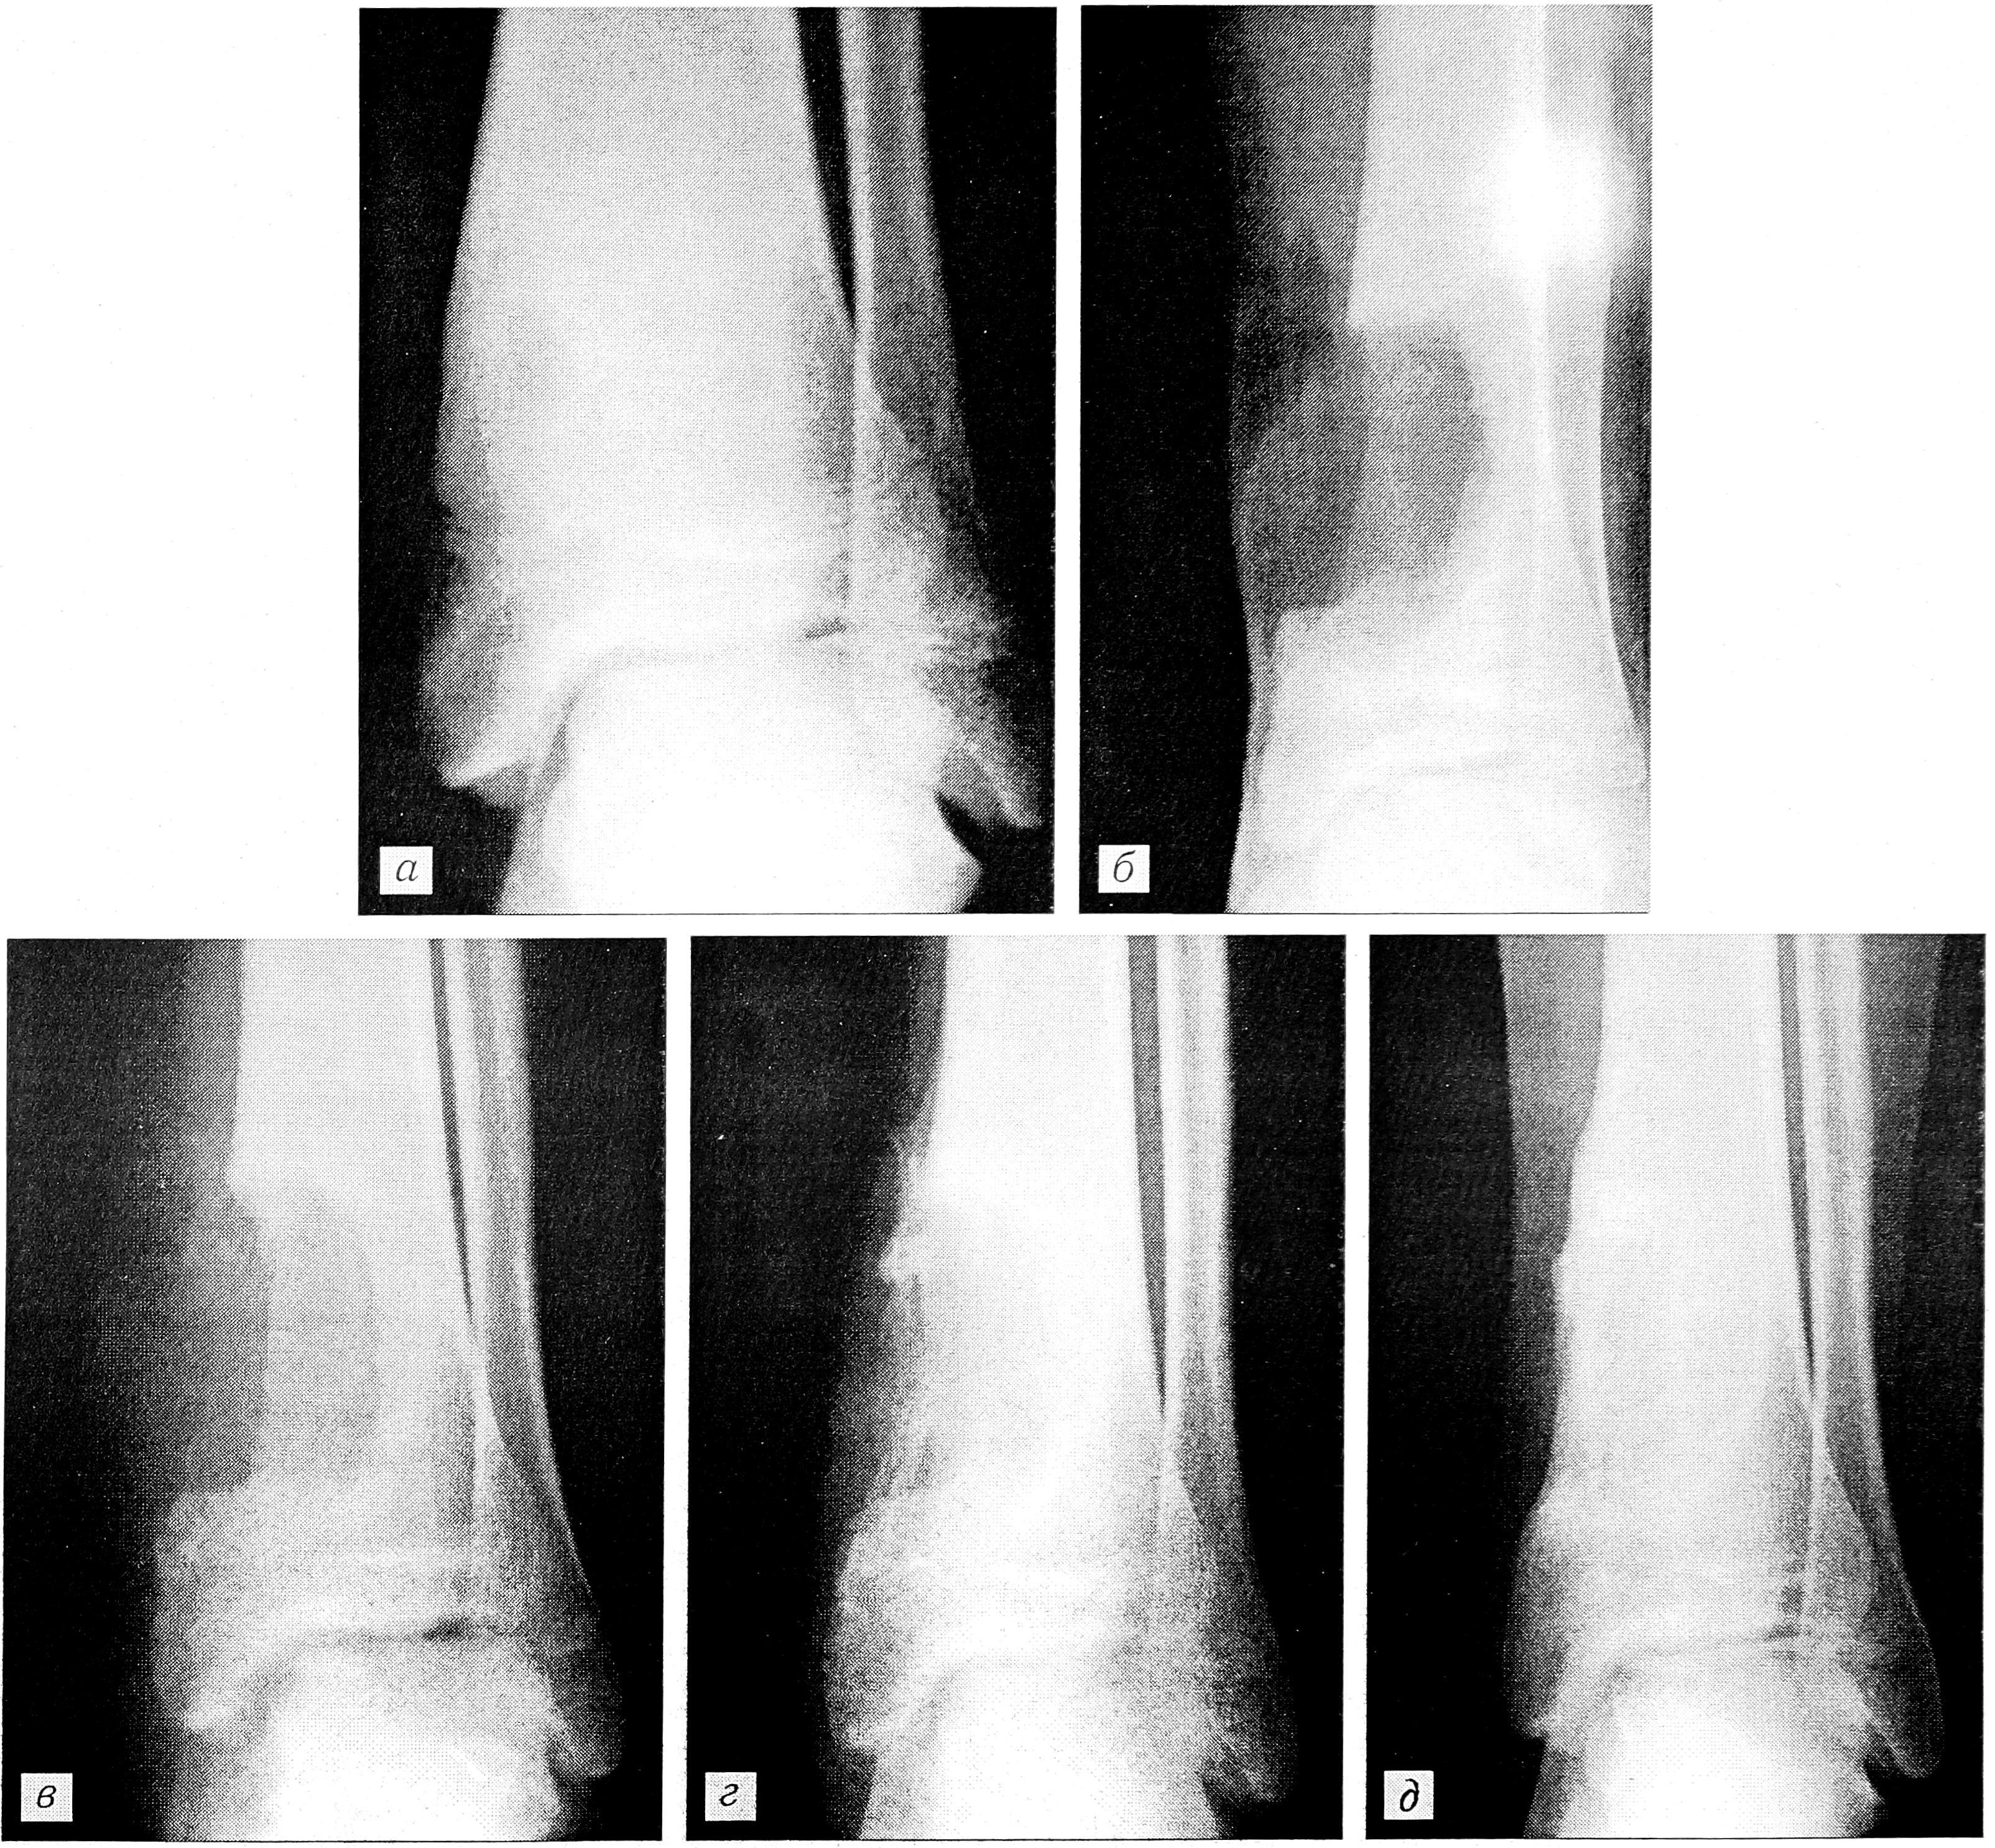

Рис. 1. Рентгенограммы больного с остеоидной остеомой нижней трети большеберцовой кости.

а — до операции, б — после выполнения краевой резекции очага с замещением дефекта аллогенным костным матриксом, в — через 3 мес, г — через 6 мес, д — через 9 мес после операции.